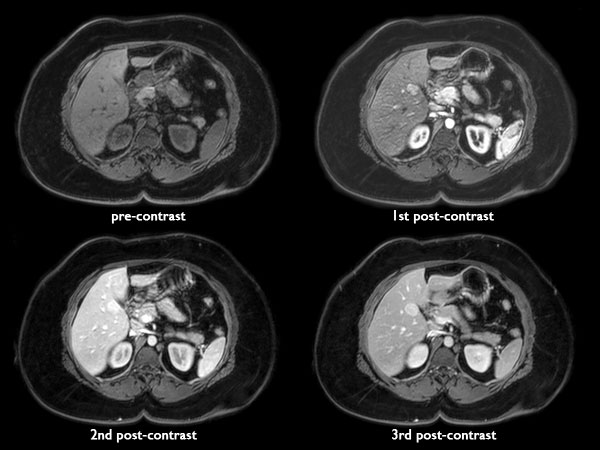

Liver imaging - Obese patient